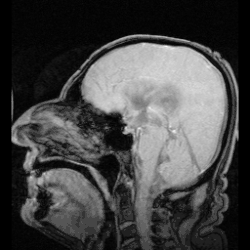

MRI showing flow of CSF

The ventricles are filled with cerebrospinal fluid (CSF) which bathes and cushions the brain and spinal cord within their bony confines. CSF is produced by modified ependymal cells of the choroid plexus found in all components of the ventricular system except for the cerebral aqueduct and the posterior and anterior horns of the lateral ventricles. CSF flows from the lateral ventricles via the interventricular foramina into the third ventricle, and then the fourth ventricle via the cerebral aqueduct in the midbrain. From the fourth ventricle it can pass into the central canal of the spinal cord or into the subarachnoid cisterns via three small foramina: the central median aperture and the two lateral apertures.

According to the traditional understanding of cerebrospinal fluid (CSF) physiology, the majority of CSF is produced by the choroid plexus, circulates through the ventricles, the cisterns, and the subarachnoid space to be absorbed into the blood by the arachnoid villi.

The fluid then flows around the superior sagittal sinus to be reabsorbed via the arachnoid granulations (or arachnoid villi) into the venous sinuses, after which it passes through the jugular vein and major venous system. CSF within the spinal cord can flow all the way down to the lumbar cistern at the end of the cord around the cauda equina where lumbar punctures are performed.

The cerebral aqueduct between the third and fourth ventricles is very small, as are the foramina, which means that they can be easily blocked.